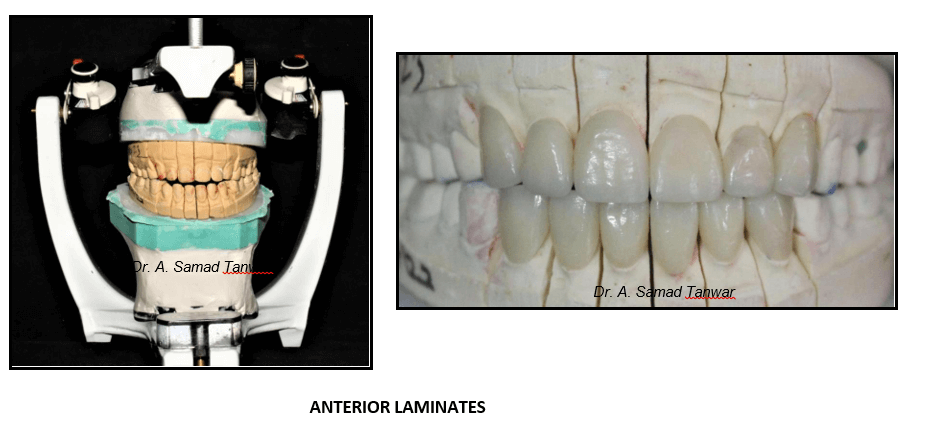

The patient was guided into centric relation and it was mounted on a semi- adjustable

The articulator was programmed using protrusive and lateral interocclusal

Impression was made of the adjusted mock-up and then it was mounted on a semi-adjustable

Customized anterior guide table was fabricated using pattern resin performing eccentric movements i.e. protrusive, right lateral and left

Lithium disilicate glass ceramic was fabricated for maxillary and mandibular Lithium disilicate (Emax) is an aesthetic, high strength material that can be conventionally cemented or adhesively bond.